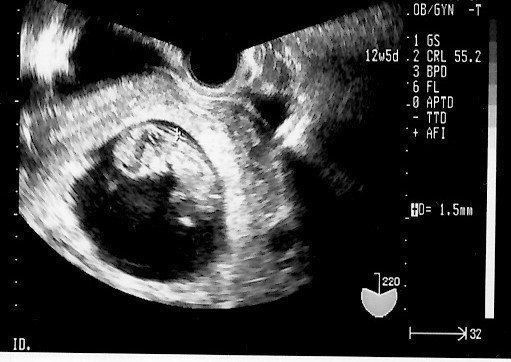

妊娠12週目のエコー写真 つわりもなく、快適なマタニティーライフを満喫

ラッキーなことに、妊娠中の私はいわゆる“つわり”の症状はなく、体調も安定していました。おかげで会社にもそれまで通り出勤していました。また妊娠中は味覚が変わるとも聞くのですが、私はそうしたことも全くナシ。さすがにアルコールは断っていたものの、「出産したらなかなか外食もできないから」を言い訳に、友人との食事会にもどんどん参加していました。